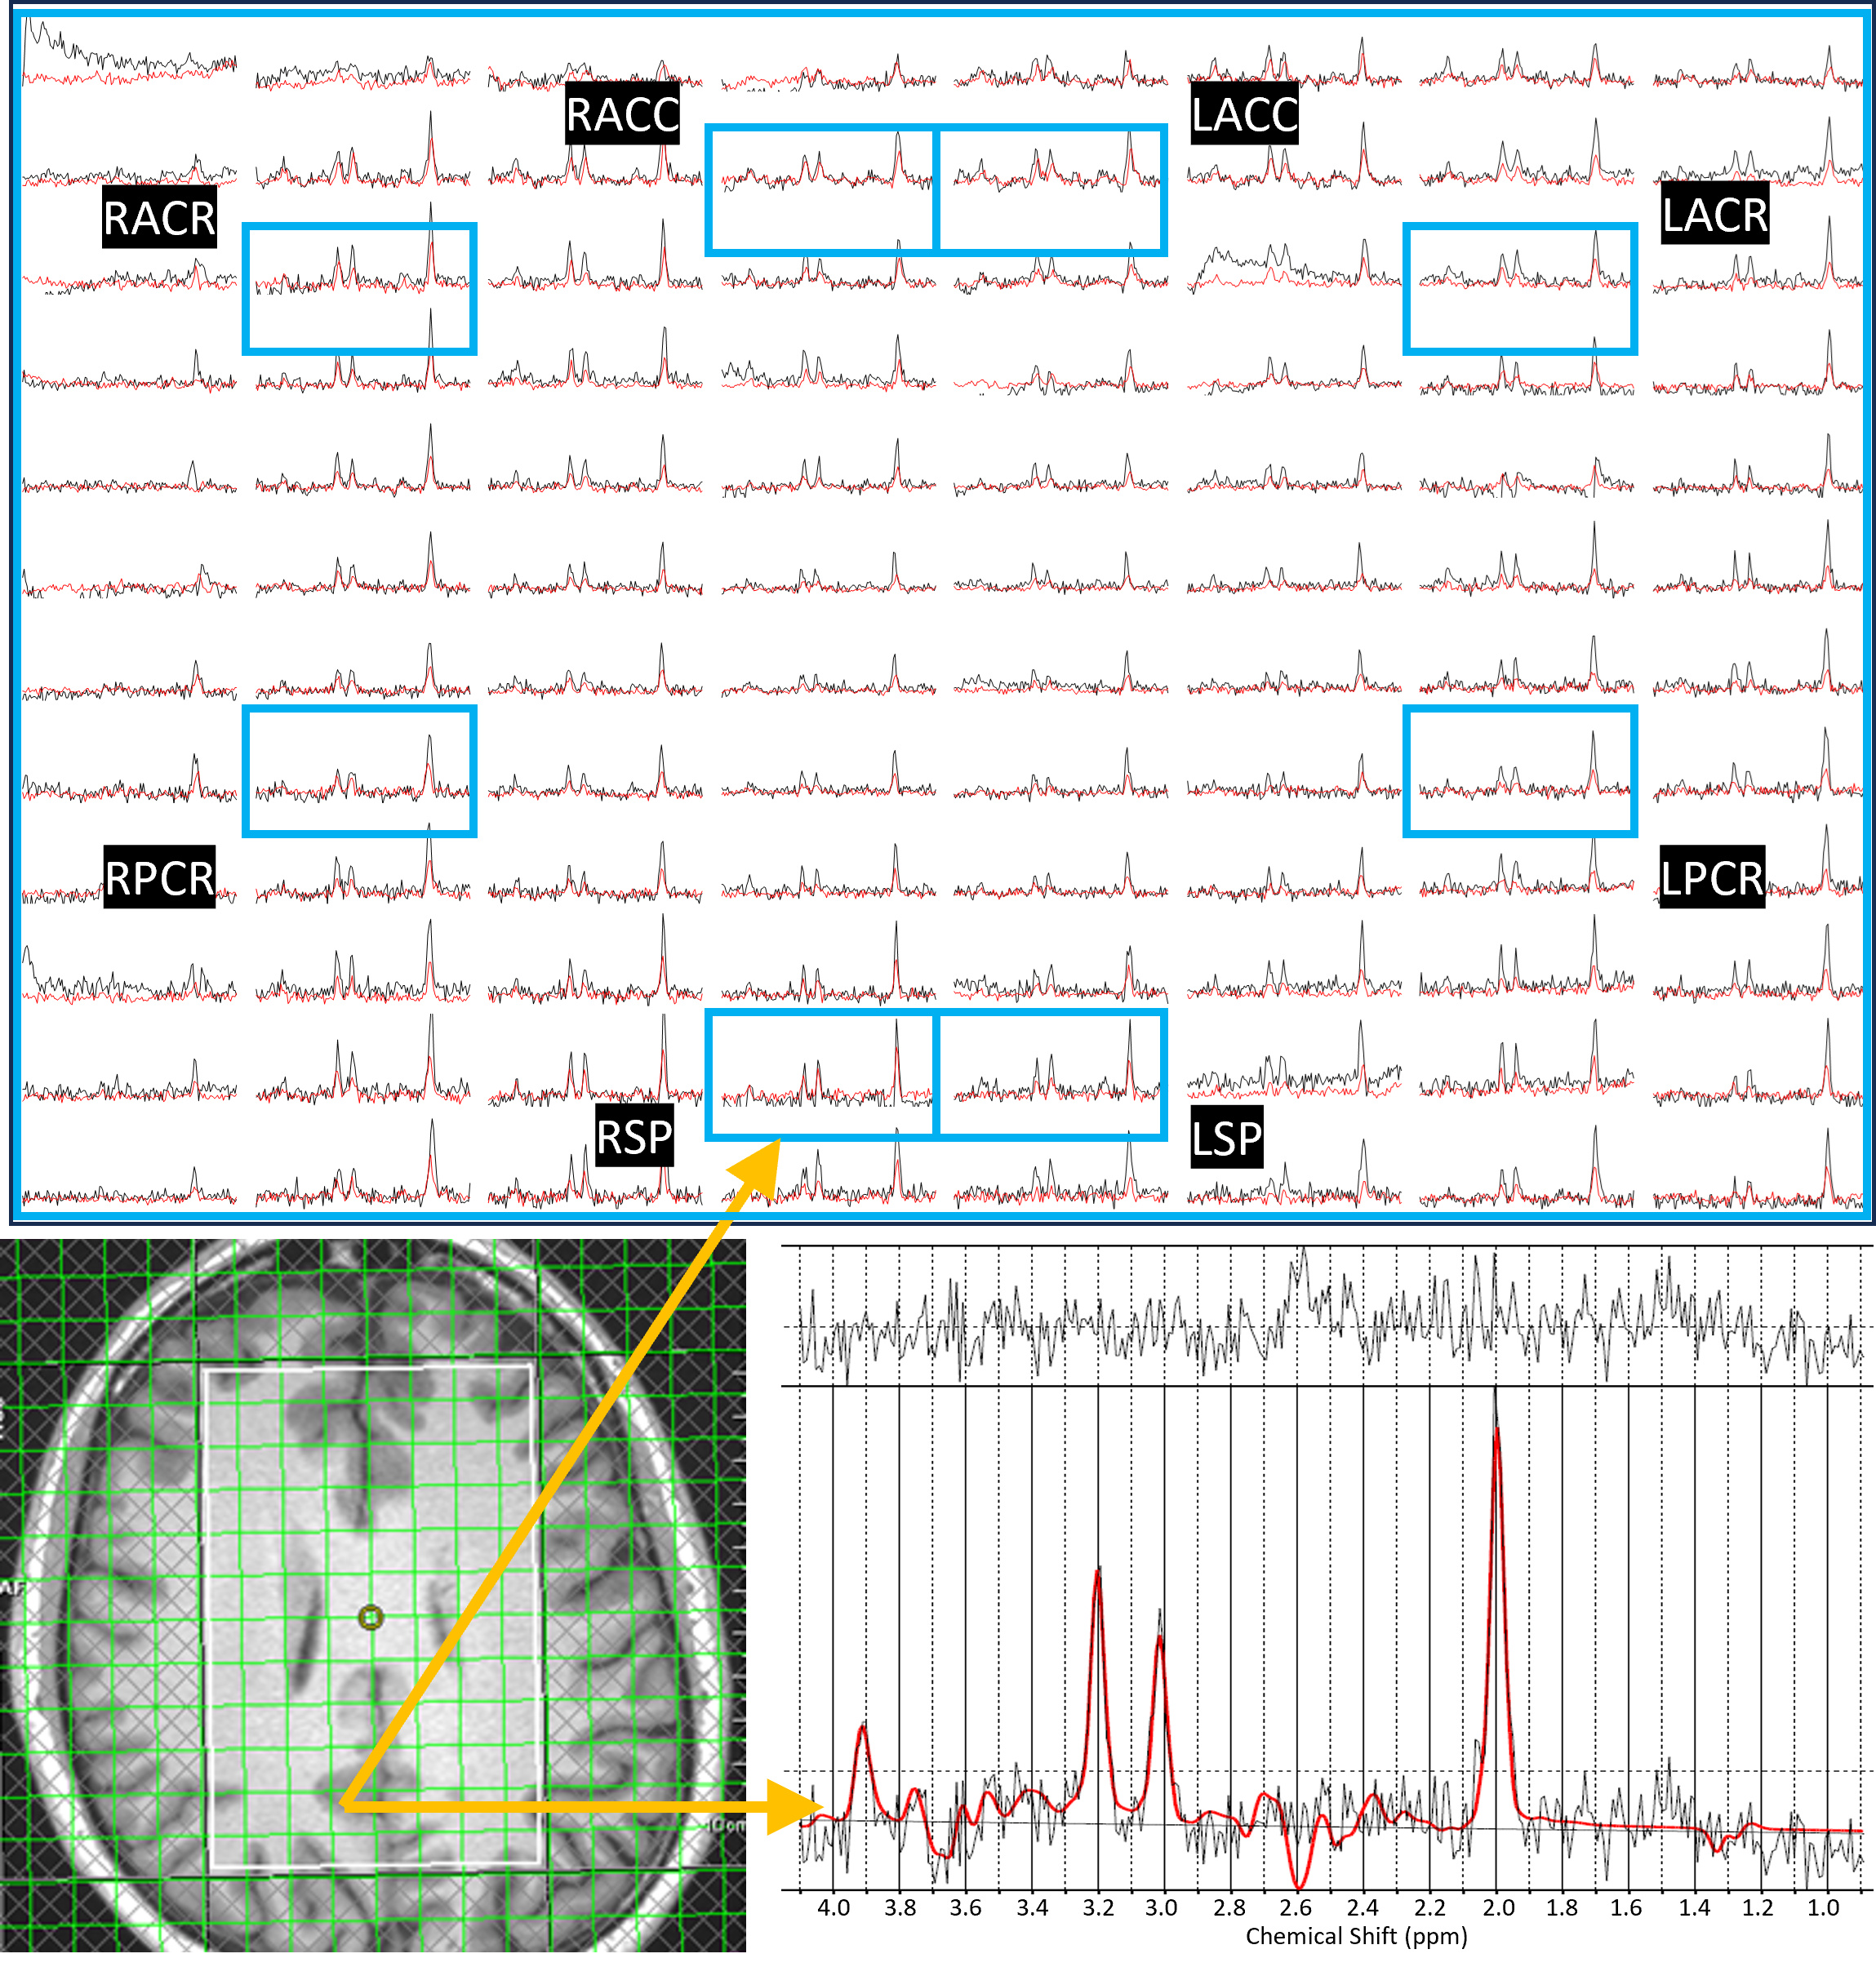

2.1. Trace-Weighted Single-Shot Diffusion Spectroscopic Imaging

2.4. Data Reconstruction and Post Processing

- Saucedo, A.; Thomas, M.A. Single-shot diffusion trace spectroscopic imaging using radial echo planar trajectories. Magn. Reson. Med. 2024, 92, 926–944. [Google Scholar] [CrossRef]

- Joy, A.; Saucedo, A.; Carmichael, R.; Daar, E.; Macey, P.; Emir, U.; Thomas, M.A. Apparent Diffusion Coefficient Measures of Metabolite in HIV: A pilot study. In Proceedings of the 32nd Annual Meeting of ISMRM, Singapore, 4–9 May 2024. [Google Scholar]